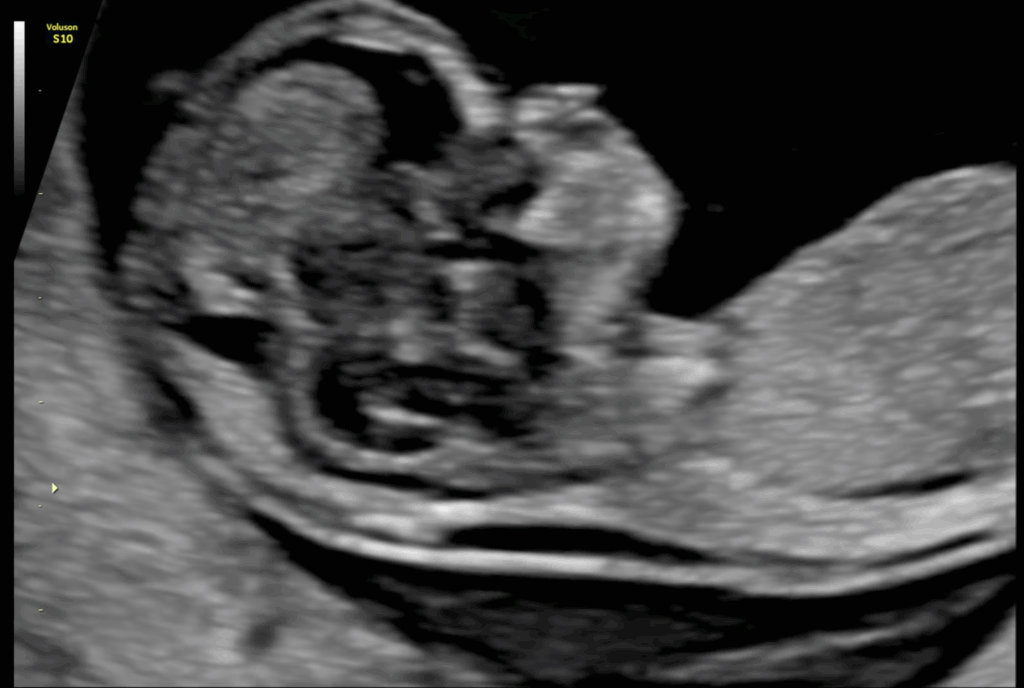

주요 장기의 형성과 위치

심장, 복부 장기 등

임신 시기에 따라 관찰 가능한 주요 장기의 형성과 위치를 확인합니다.

각 장기가

해당 시점에서 기대되는 모습으로 발달하고 있는지를 평가합니다.